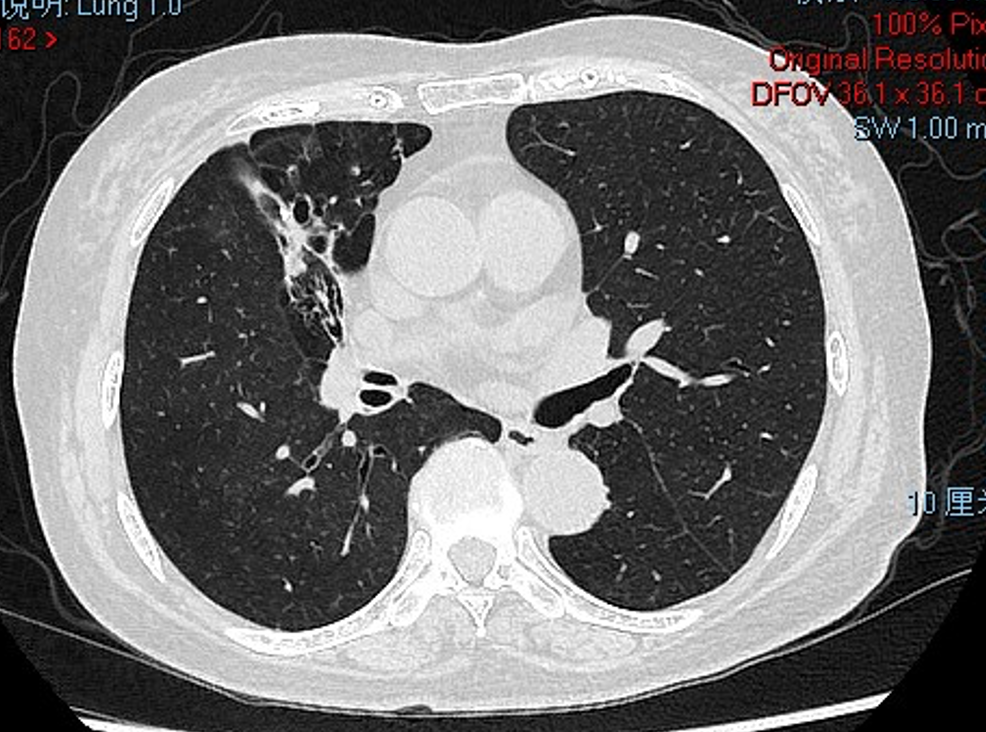

胸部CT(2021-2-23)